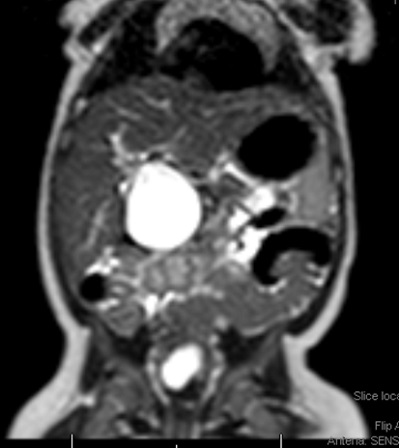

Se realiza ecografía abdominal (Fig. 1), donde se objetiva una marcada dilatación del colédoco, con morfología quístico-fusiforme, que se extiende desde hepático común hasta región pancreática, sugestivo de quiste de colédoco tipo IA según la clasificación de Todani, con barro biliar y leve ectasia de la vía biliar intrahepática. Se completa el estudio con una colangiorresonancia magnética (Fig. 2), donde se visualiza una lesión quística bien definida y redondeada del conducto colédoco en su totalidad, de 4,6 × 3,5 × 3,3 cm, sin extensión a vía biliar intrahepática, confirmando la sospecha diagnóstica inicial.

| Figura 2. Colangiorresonancia magnética. Lesión quística bien definida, amplia, y redondeada del conducto colédoco en su totalidad |